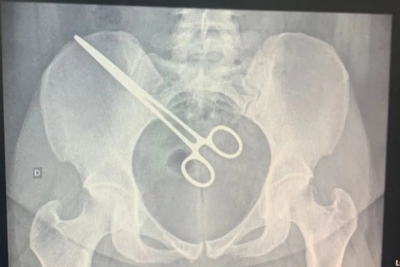

Mulher fica 2 meses com pinça esquecida dentro do corpo após cirurgia